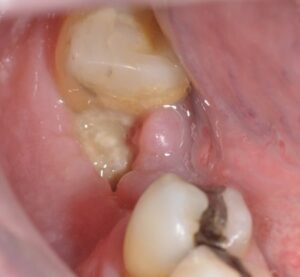

نمو العظام غير الطبيعي  (Exostosis Tori)

النمو الزائد للعظم، الذي يسمى “إكزوستوسيس”، يمكن أن يسبب البروز، يحدث هذا النمو عادةً في الجزء الداخلي من الفك السفلي (mandibular) أو الفك العلوي ويكون غير مؤلم. أسبابه وراثية أو بسبب الضغط المستمر، ويُلاحظ غالبًا عند البالغين ولا يحتاج إلى علاج، إلا إذا تسبب في تمزق اللثة.

ورم أو كيس

ورم أو كيس في الفك يمكن أن يؤدي إلى بروز العظم. هذه الحالات نادرة، ولكن إذا لاحظت تورمًا أو نموًا سريعًا، يجب إجراء خزعة للتأكد.